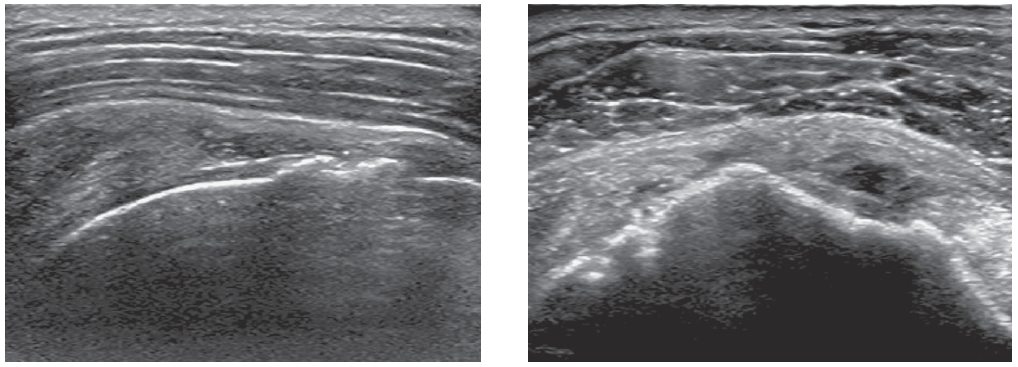

1. 위 사진은 전외측 어깨의 종방향(우측면이 외측)과 횡방향(우측면이 전방) 초음파 영상이다. 무엇을 발견할 수 있는가?

☞ 점액낭에서 관절면으로 이어진 회전근개의 저에코 부위를 발견할 수 있다.

2. 이는 무엇을 의미하는가?

☞ 수축(Retraction)을 동반한 극상근건의 완전 파열을 의미한다.

이 환자는 극상근건의 관절와상완관절과 견봉하점액낭이 소통된 전층파열(full-thickness tear)을 가지고 있다. 어깨의 초음파검사는 회전근개의 이상을 평가하는데 탁월하고 빠른 검사방법이다. 극상근건은 상완골에 직접적으로 위치한 곳에서 고음영과 섬유성으로 나타난다. 연골의 무에코성의 테두리는 고에코성의 골피질을 덮고 있다. 제어코의 삼각근은 피하지방의 바로 밑에 있다. 그 아래에 있는 것은 점액낭 주위 지방으로 둘러쌓인 무에코성의 점액낭이다. 가운데에는 극상근이 승모근과 견갑골 사이에 존재한다.

회전근개 전층파열은 저에코성 또는 무에코성의 결손 구조로 나타나는데, 액체가 찢어진 힘줄을 대체한 것이다. 이 액체는 연골을 고에코성으로 강조하는 초음파의 투과도가 두드러지게 나타난다. 이는 이중 피질 모양을 만들어 내는데, 두개의 고에코 평행 선 또는 연골경계부 징후를 가진다. 압박은 점액낭주위 지방을 힘줄 틈으로 만들 수 있는데, 이를 새깅 점액낭주위 지방 징후(sagging peribursal fat sign)이라 부른다. 힘줄의 비가시화는 매우 크고 수축된 힘줄을 암시한다. 근육의 위축은 근육의 전반적인 에코발생도를 증가시킬 수 있다.